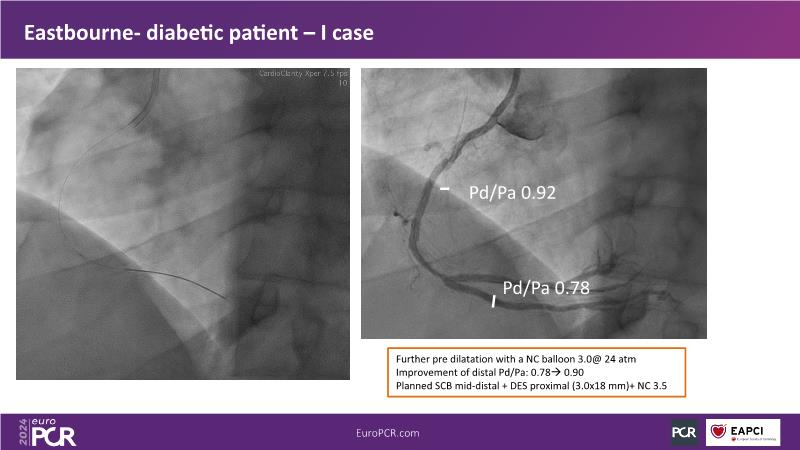

Browse this EuroPCR 2024 session to explore the safety and efficacy of sirolimus-coated balloons from pre-clinical data, review MagicTouch data from real-world populations with case-based examples, and learn about the MagicTouch sirolimus-coated balloon clinical programs. Discover insights and takeaways from the significance of the EASTBOURNE subgroups, and analyze the challenges and opportunities in PCI for diabetic patients.